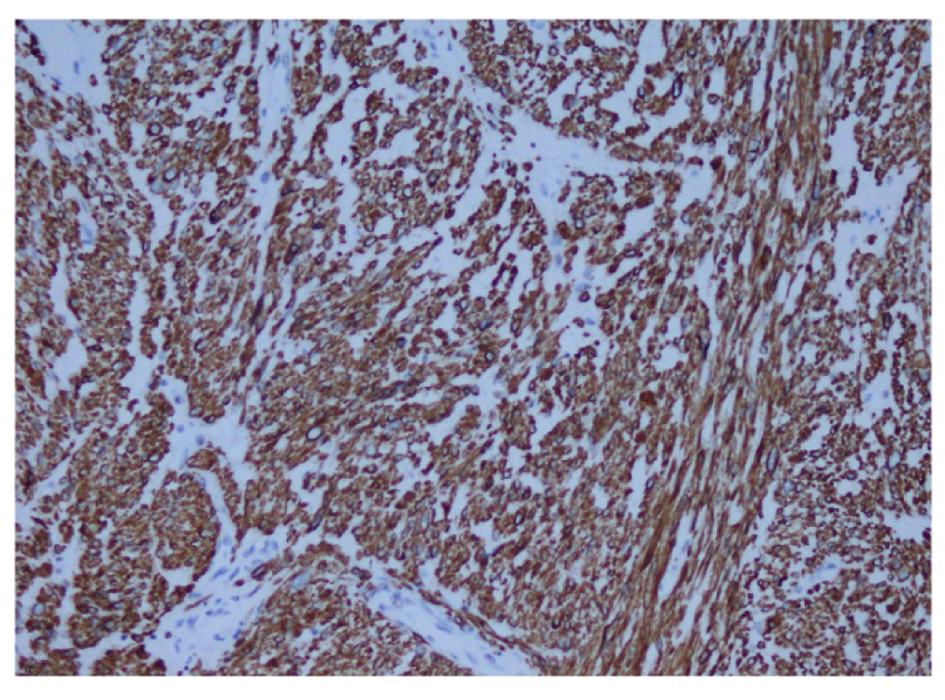

Pathological examination revealed primary high-grade renal leiomyosarcoma. Macroscopic findings were as follows: A tumor with the biggest diameter of 8 cm was seen on the renal hilus which was pinky-yellow in color, well-circumscribed and showing hemorrhages and cystic features in a focal area (Fig. 3). Microscopic examination reported that pleomorphism (small picture) and necrosis (blue arrow) were remarkable in the tumor consisting of the cells with pink cytoplasm and spindle nucleus crossing with each other from several angles. Rates of necrosis and mitosis were 16-20/10HPF (Fig. 4) (H&E, × 100, 200). In the immunohistochemical examination DKA was positive, desmin (+), CD117 (-), CD34 (-) and S-100 was (-) (Fig. 5, 6). Ki-67 proliferation index was found to be 15%. No distant metastases were found on the PET/CT. The patient was placed in follow-up program.

![]() Click for large image | Figure 5. Immunohistochemistry showing diffuse actin expression in smooth muscle fiber cytoplasm. Actin (× 200). |